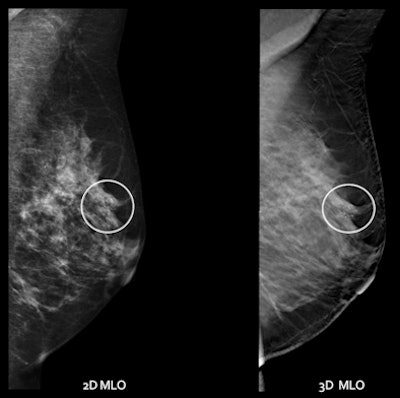

![]() |

| Digital mammography and DBT, mediolateral oblique view. |